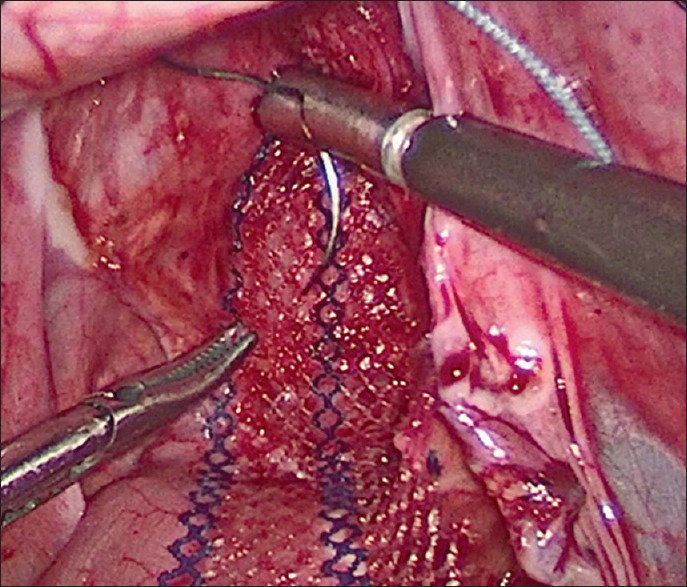

Background: Rectal prolapse is a relatively common, usually self-limiting illness in children. Peak incidence is between 1 and 3 years. The primary treatment of rectal prolapse is non-operative. Surgical intervention is needed in long-standing intractable cases of rectal prolapse, rectal pain/bleeding/ulceration and prolapse that needs frequent manual or difficult reduction. The aim of this study was to compare the efficacy and outcome of laparoscopic ventral mesh rectopexy versus laparoscopic suture rectopexy in the management of persistent rectal prolapse in children not responding to conservative management and/or recurrent after sclerotherapy or anal encirclement.

Materials and methods: Twenty-four cases were randomised into two groups at the ratio of 1:1, Group 1 patients were managed by laparoscopic ventral mesh rectopexy, whereas Group 2 cases were managed by laparoscopic suture rectopexy. Patients with primary surgical conditions such as anorectal malformations, Hirschsprung's disease, rectal polyps or masses and Ectopia Vesicae were excluded from the study. Inclusion criteria were complete rectal prolapse cases with failed medical treatment for at least 6 months and/or recurrent after injection sclerotherapy or anal encirclement.